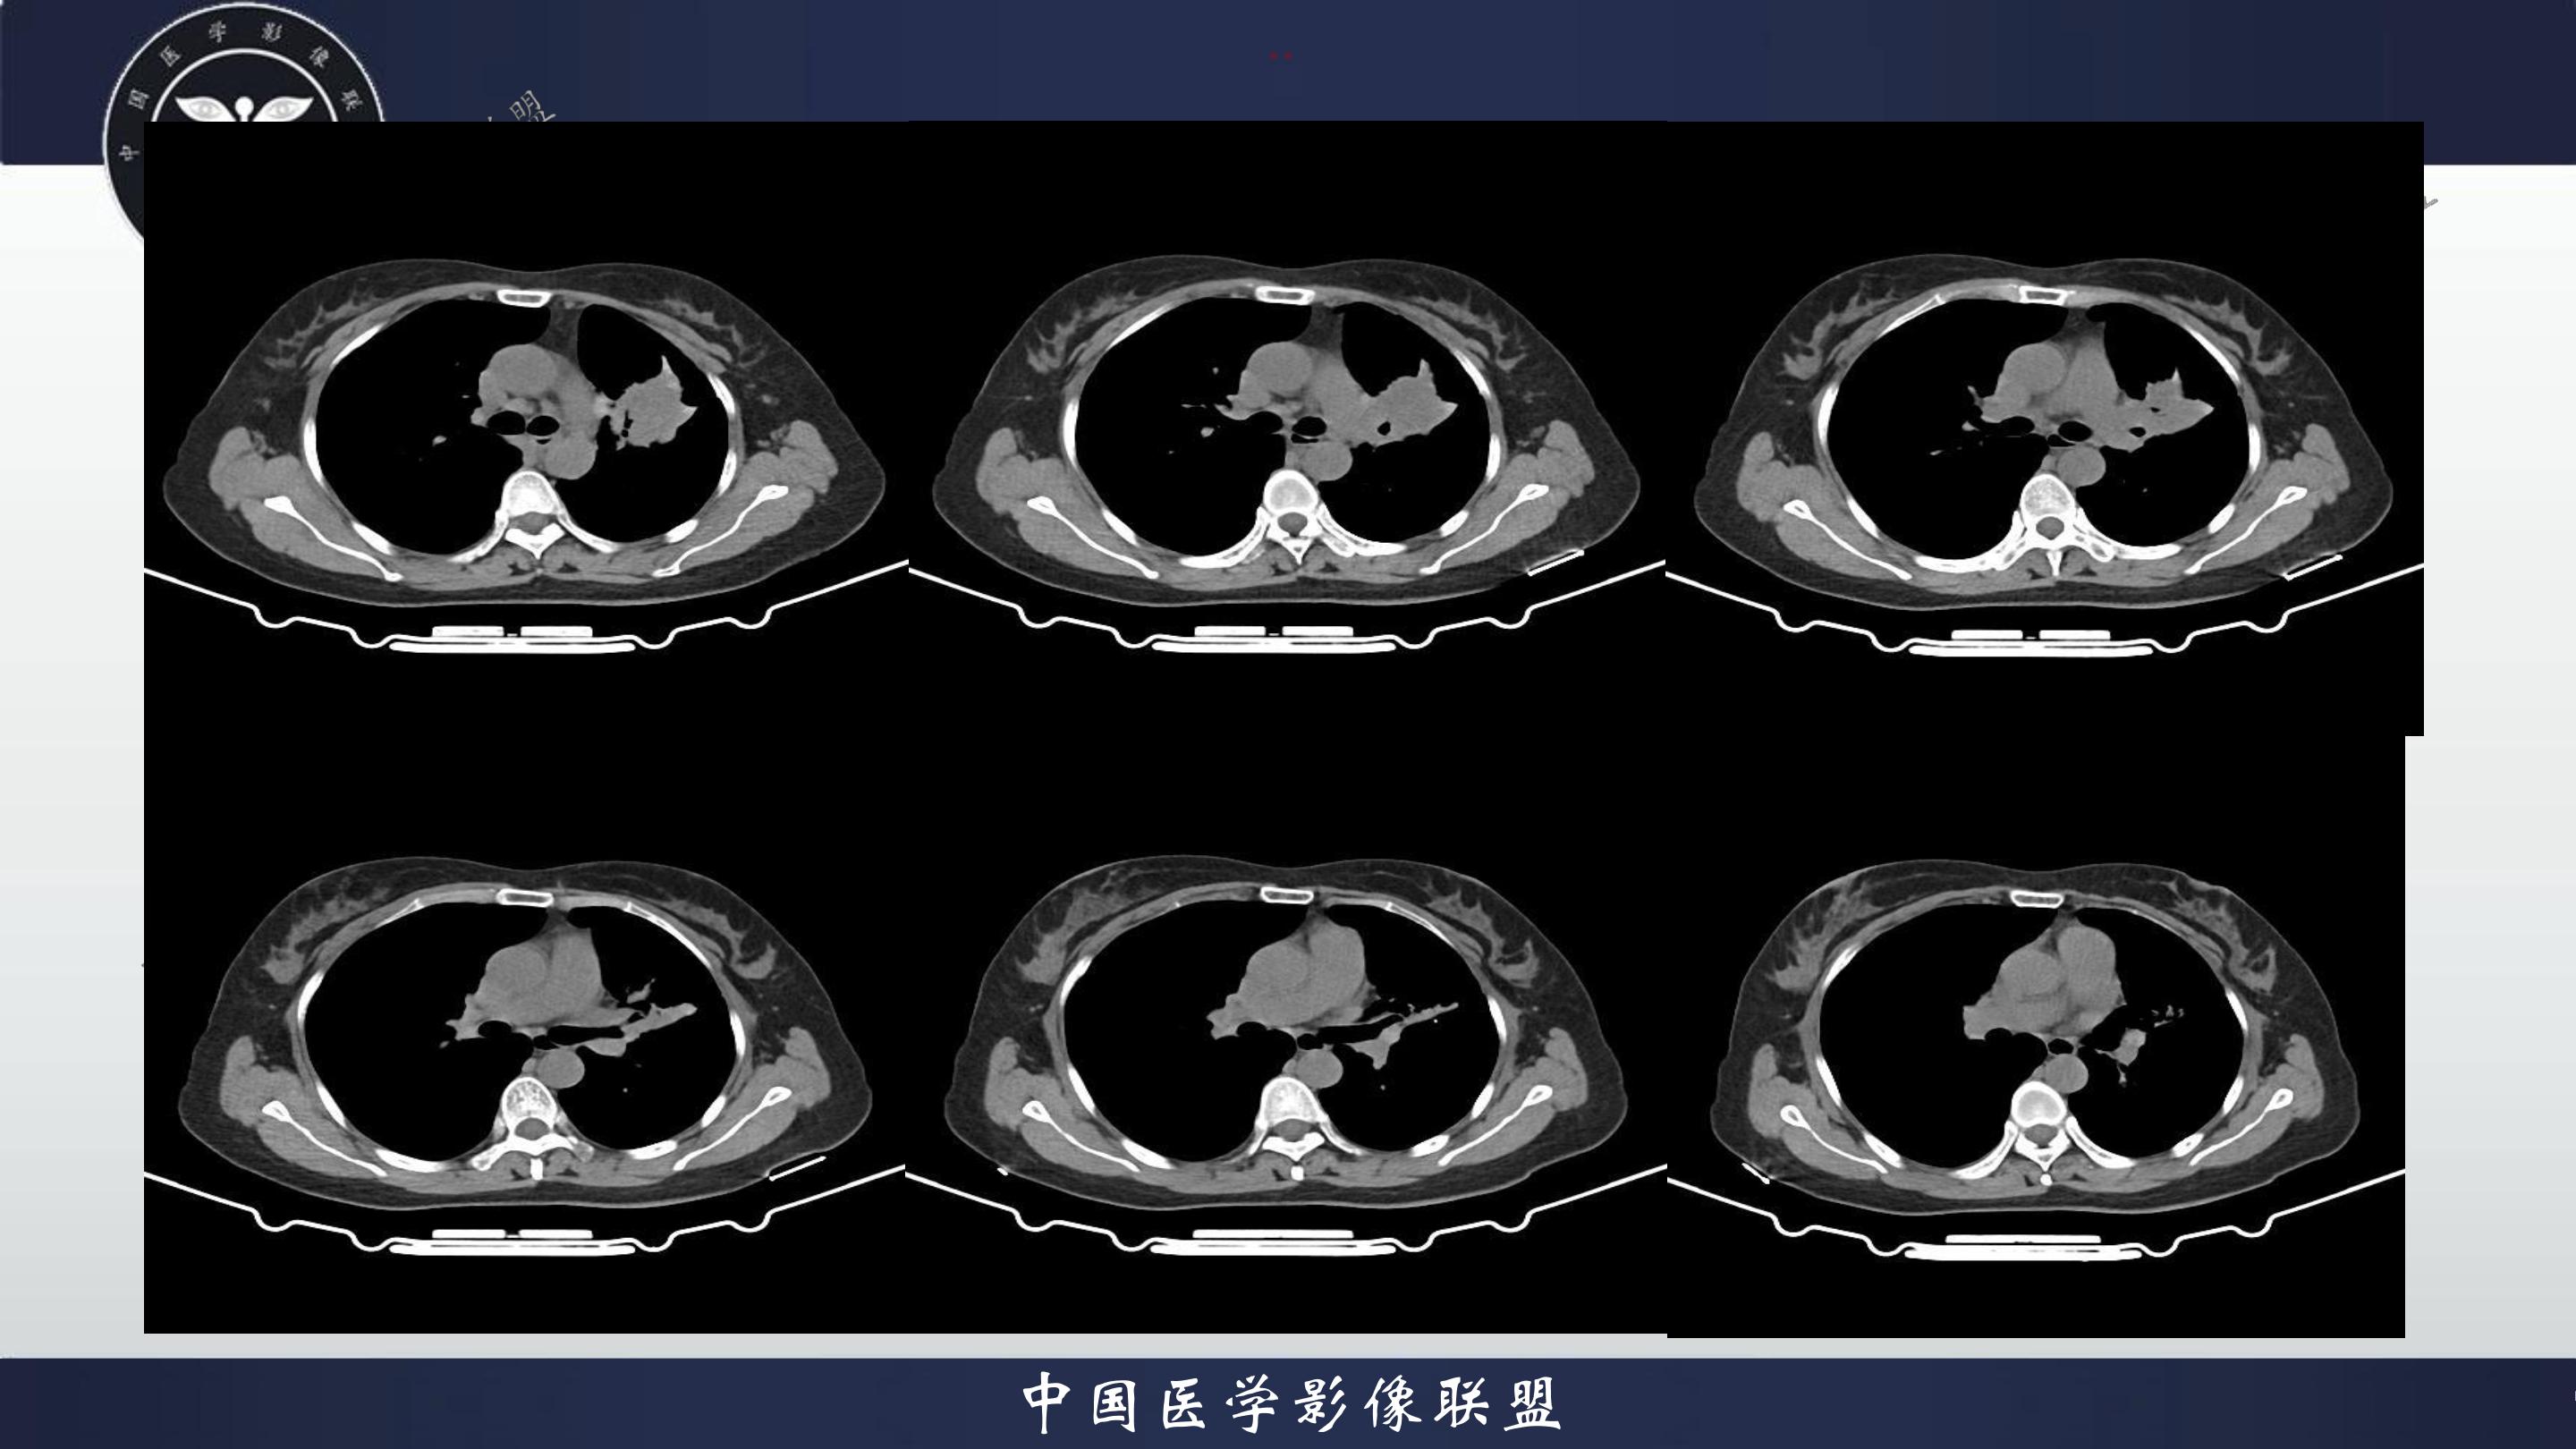

老年女性,咳嗽、咳痰伴痰中带血3月

3月前患者无明显诱因出现咳嗽、咳痰,呈阵发性咳嗽,咳大量黄色脓痰,痰不易咳出,伴痰中带血,量少,具体量不详,伴鼻塞、口干、乏力,活动后感喘息、劳累,休息后缓解,无发热、畏寒,无盗汗,无心慌、胸闷,无腹痛、恶心、呕吐,无头昏、心前区压榨性不适,院外予以输液及口服药物治疗后症状无明显缓解,现为系统诊治就诊我院门诊,门诊以“社区获得性肺炎”收入我科。病来精神、饮食、睡眠尚可,大小便正常,体重无明显变化。

既往有高血压病史10+年,血压最高160/70mmhg,自诉长期口服降压药物治疗,具体药物名称不详;8+年前患者有胆囊结石病史,自诉当时予以手术治疗后好转出院,具体不详;否认“糖尿病、冠心病"等疾病史。否认“肝炎、伤寒、结核”等传染病史;否认已知药物及食物过敏史,否认烟酒史

查体:T:36.8℃P:82次/分,R:20次/分,BP:135/82mmHg,spo2:96%.神清合作,咽稍充血,双侧扁桃体无肿大;双肺呼吸音粗,双肺可闻及少许湿性啰音,未闻及哮鸣音;心界不大,心率82次/分,律齐,心音低钝,各瓣膜听诊区未闻及杂音,腹软,中上腹压痛,无反跳痛及肌卫,肝脾未扪及。双下肢无水肿。

4.辅查:生化报告(2024-11-14 13:06:51)尿素氮或尿素:10.1mmol/L↑,尿酸:342umol/L↑,钾离子:3.16mmol/l↓,尿常规报告(2024-11-14 13:11:41)隐血:+2,凝血报告(2024-11-14 13:16:37)血浆D-二聚体测定:0.62ng/mL↑,生化报告单(2024-11-14 16:14:45)MP滴度(1:40):弱阳性,PCR报告(2024-11-14 16:50:37)人鼻病毒核酸(HRV-RNA)定性:阳性,传染性指标、粪便常规、BNP、心肌特异蛋白、CEA、肝功能、血脂、红细胞沉降率未见明显异常。血气分析回示:PH 7.443 PCO2 28.3mmhg PO2 90.9mmhg HCO3- 19.53mmol/L 氧和指数432.9mmhg;心电图回示:1.窦性心律2.T波改变(Ⅲ倒置、aVF低平)